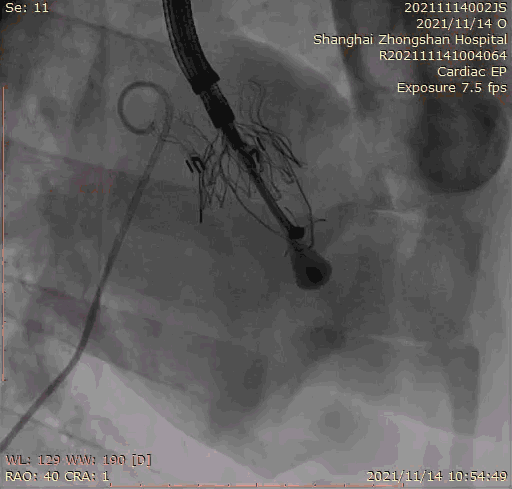

本次臨床前研究經(jīng)右側(cè)頸靜脈置入LuX-Valve Plus輸送系統(tǒng)可調(diào)彎鞘管,在DSA及超聲引導(dǎo)下將人工三尖瓣瓣膜植入到原有三尖瓣位置,利用獨(dú)特的錨定技術(shù)將人工瓣膜支架可靠固定在預(yù)定的位置。